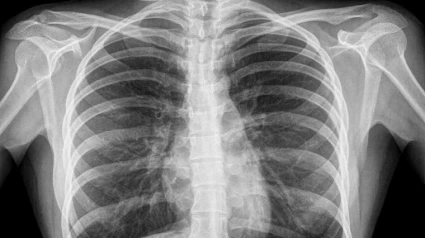

Roberto Pablo explica los riesgos a los que nos sometemos cuando nos hacemos una radiografía o mamografía. Fran Valiño cuenta hasta dónde llegamos para robar cosas de los hoteles. Los chicos de la asociación "Música en Vena" nos presentan su proyecto. David Otero trae las efemérides del día.